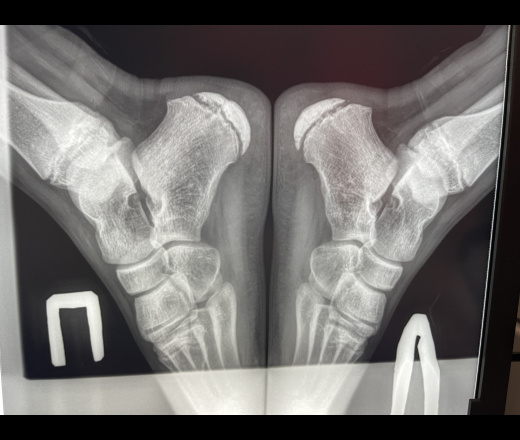

Болезнь келлера мкб